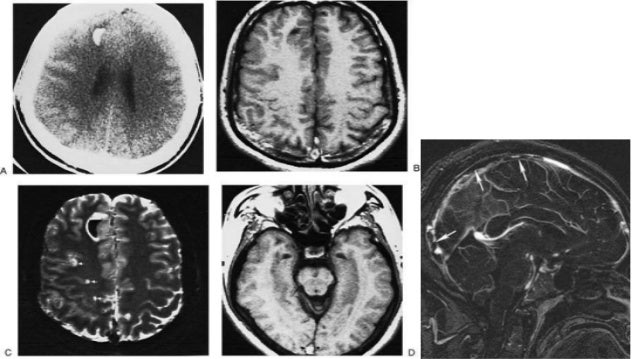

Imaging of acute stroke , Interventions

Acute infarction | Image | Radiopaedia.org

Acute Brain Infarction – Something About Radiology – Just ...